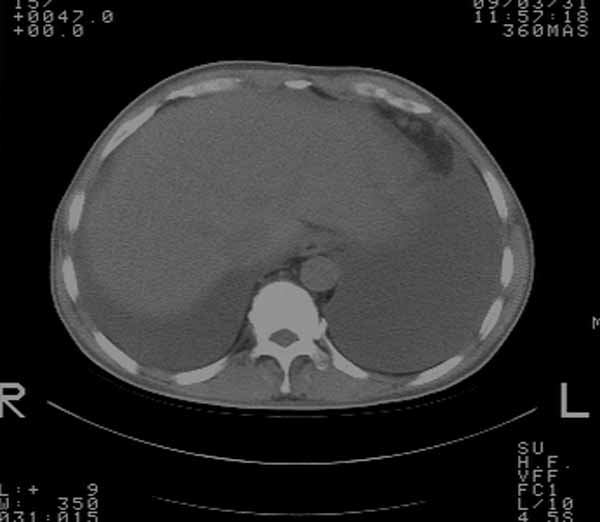

以下是引用余辉在2009-3-31 18:43:00的发言:[br]肺水肿,双侧心腔积液,心包积液,心影增大,疑似心衰

以下是引用wangyong1977在2009-3-31 20:46:00的发言:[br]肺水肿,双侧胸腔积液,心包积液,心影增大,疑似心衰 [br]

以下是引用宇宙ct在2009-3-31 18:57:00的发言:[br]肺水肿,双侧心腔积液,心包积液,心影增大,疑似心衰 [br] [br]